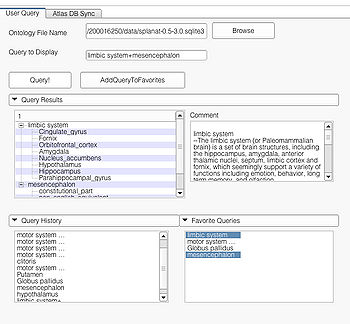

The GUI consists of two main panels. The "User Query" page and "AtlasDBSync" page. The "User Query page" is where the user interacts with the visualizer to produce the visualizations. The "AtlasDBSync" page helps to integrate the ontology with the 3D models contained in the atlas. The visualizer module automatically tries to find appropriate mappings of the 3D models with the ontology. But for models where exact matches aren't found, the visualizer module tries to find all the matching entries from the DB. The interface in the "AtlasDBSync" page allows user to check the mappings found by the module and set up the correct mappings between the ontology and the DB.

User Query Page

This page is useful for creating visualizations based on user typed queries. The user inputs consist of the Ontology File Name and Query To Display. The button Query fires a query and causes the module to start processing the user query for visualization. The button AddQueryToFavorites adds the last typed user query to the list of favorite queries. The favorite query list is shown in the bottom panel Favorite Queries. Additionally, the interface also shows a history of typed queries in the panel Query History.

The Query Results panel shows the result of a query, consisting of all the associated predicates and parts for the query. The Figure User Page GUI shows the result of a simple query "limbic system".Additionally, the interface also shows a Comment that contains any relevant textual information about the query obtained from the ontology. The user can refine a search by selecting from the query result. Optionally, the user can also select by clicking on any selection from the Query History or Favorite Queries panel to redo search and visualization. The interface supports the multiple selections to form complex queries. The visualization resulting by searching with the query "Limbic system" is shown below.